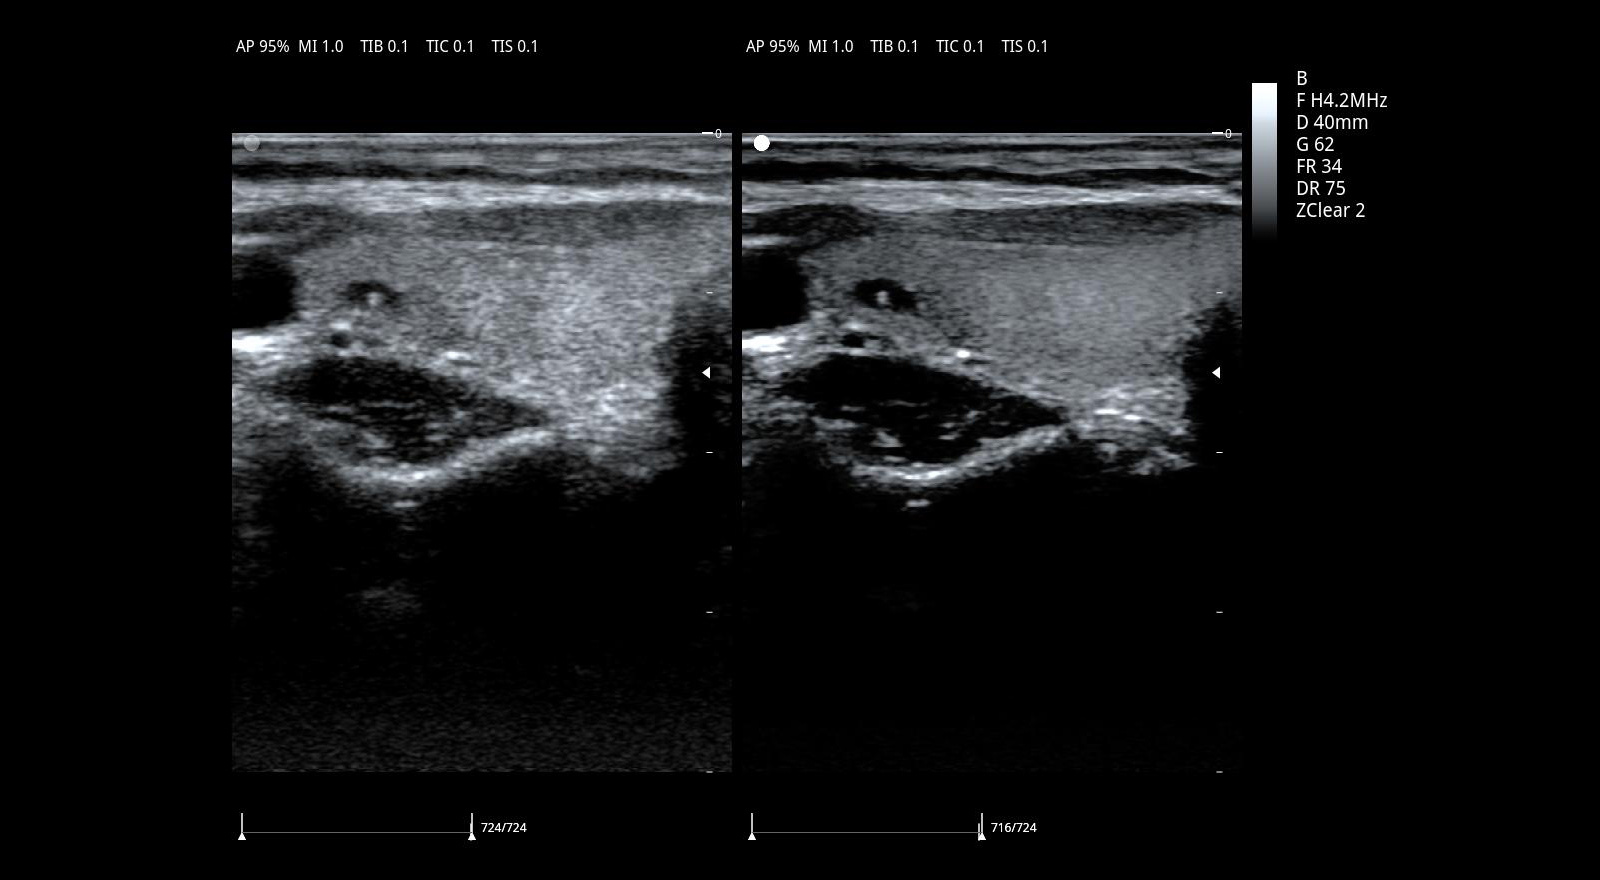

Imágenes con filtro espacial adaptativo – zonClear

ViV 20 está configurado con un algoritmo avanzado de filtro espacial adaptativo y se combina con una técnica de filtrado temporal con compensación de movimiento. Reduce eficazmente el ruido de speckle y mejora significativamente la visualización de los límites tisulares y la visualización del eco tisular mediante la detección de la ubicación de los límites anatómicos.

Imágenes armónicas por inversión de pulso PIHI

Con PIHI, se transmiten simultáneamente dos ondas de pulso con fase opuesta, se activa el procesamiento de superposición de ecos y se cancela la señal de las formas de onda fundamentales, generando ondas armónicas de 6 dB. PIHI reduce eficazmente el ruido de moteado y mejora significativamente el contraste y la resolución de la imagen.

Imágenes clínicas extraordinarias